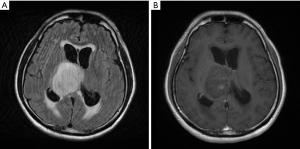

A 44-year-old man presented to our hospital with 2 weeks of severe headache, progressive unsteady gait and dizziness. Mild slurred speech was also found by the family for about a month. There was no sensory or motor function impairment, language function impairment, memory loss, arrhythmia, change in urination frequency, change in bowel habit, or change in visual fields. MRI showed an ovoid long T2 lesion with faint scattered contrast enhancement arising from right side of 3rd ventricular region, measuring 53 mm × 46 mm in diameter, majorly involving right thalamus, and causing obstructive hydrocephalus (Figure 1). Brain tumor was first suspected with increased intra-cranial pressure (IICP). The neurological symptoms of the patient mentioned above, including headache, unsteady gait and dizziness, recovered with controlling the IICP by steroids and glycerol. Only slurred speech continued after the IICP was controlled. The patient’s Karnofsky score was 90 and Eastern Cooperative Oncology Group (ECOG) performance score was 1 before any treatment started.